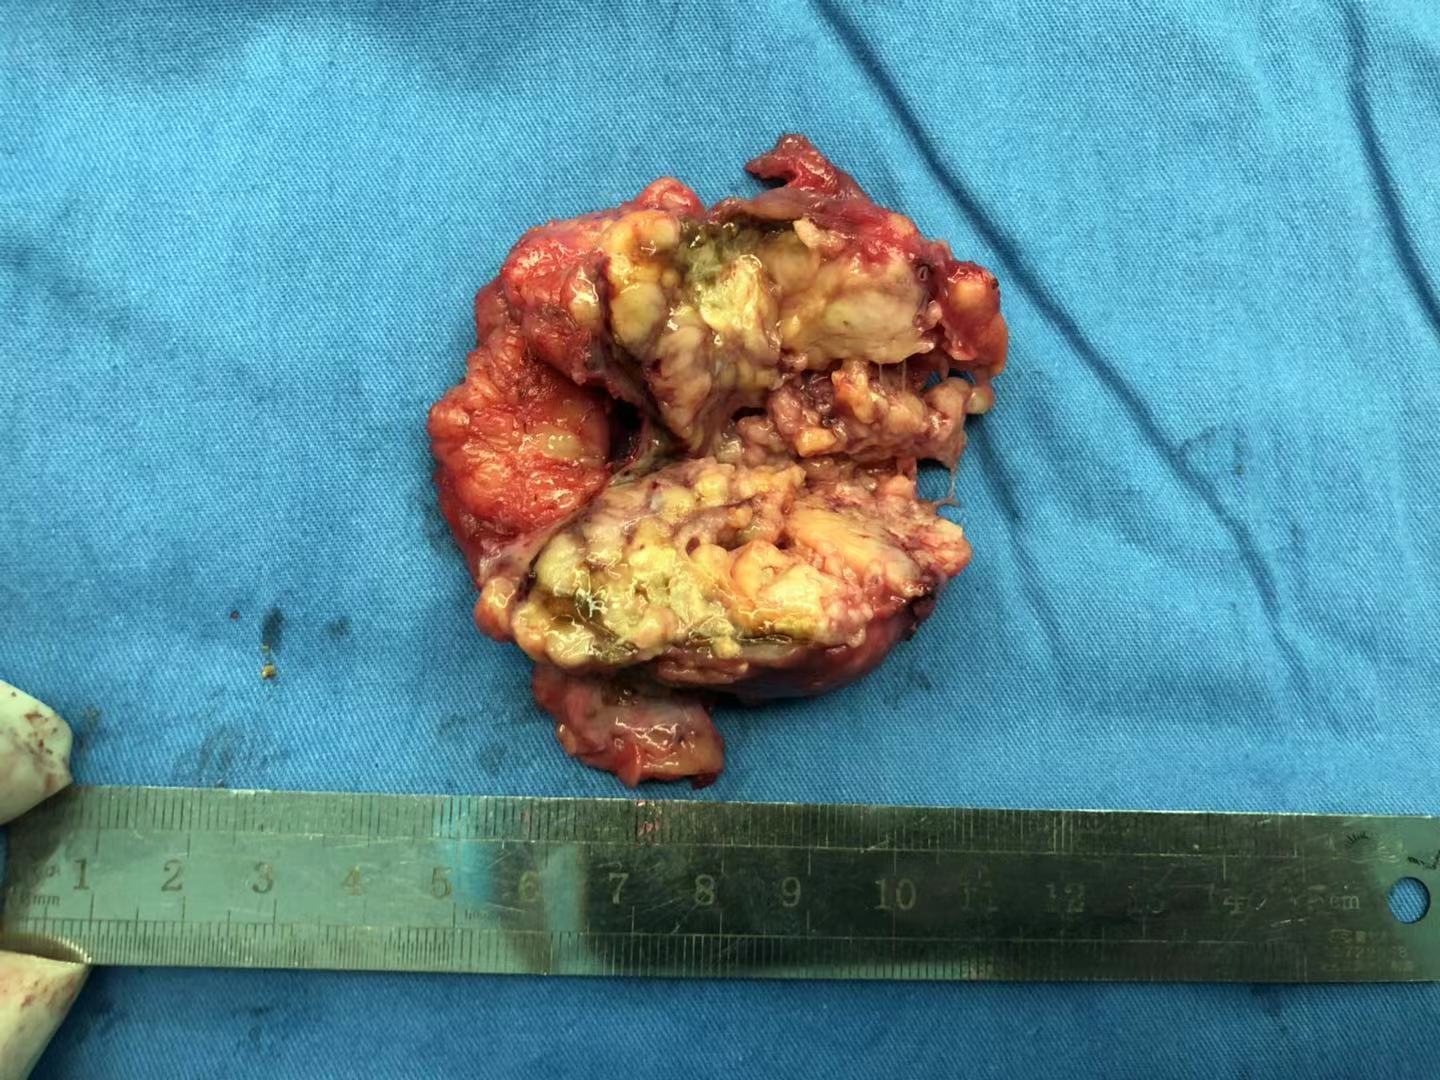

错构瘤破裂出血,也能腔镜完成

我的手术案例四肾错构瘤自发性破裂后行肾部分切除术一例